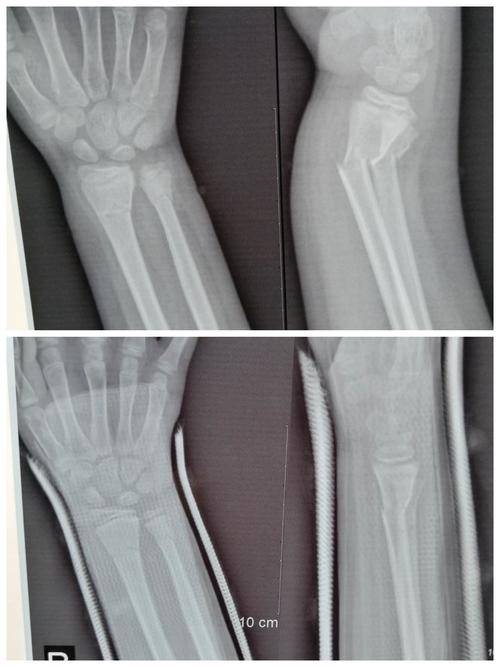

(四)2020-06,儿童尺桡骨远端骨折 经手法整复,小夹板固定.

儿童桡骨远端骨折